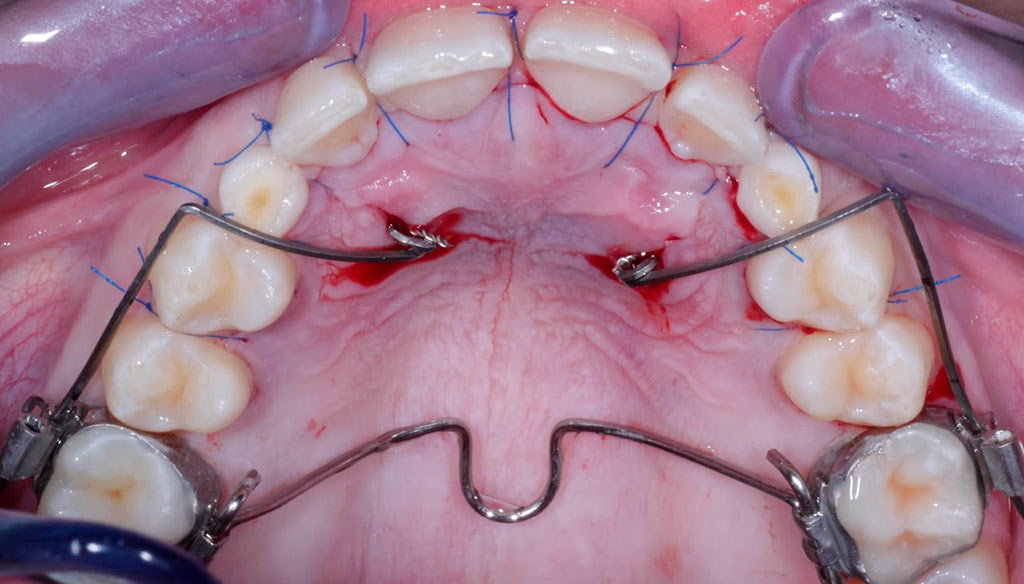

Tracción de canino con k9